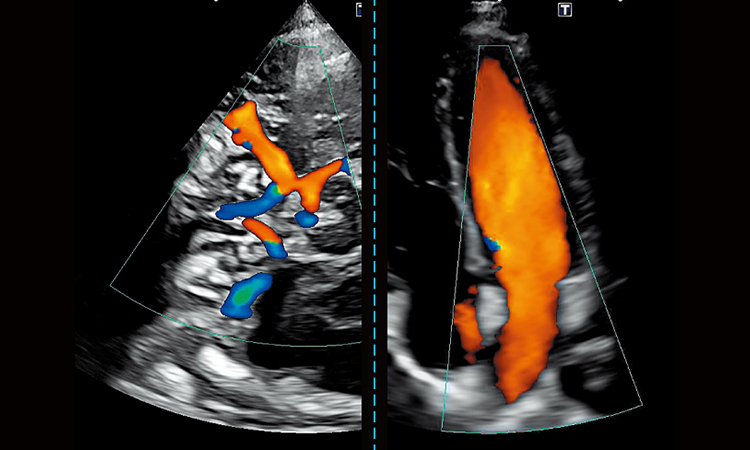

Shear Wave Elastography per valutazioni tissutali quantitative

Advanced Doppler per flussi lenti e microvascolarizzazione

Valutazione cardiovascolare e addominale di alto livello